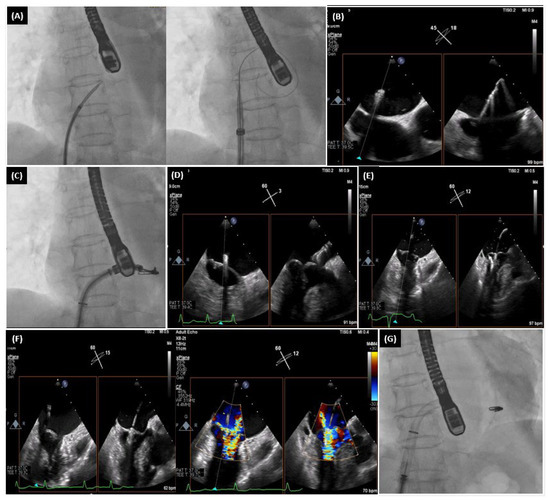

- Drakopoulou, M.; Latsios, G.; Synetos, A.; Benetos, G.; Soulaidopoulos, S.; Oikonomou, G.; Apostolos, A.; Aggeli, K.; Lozos, V.; Lymperiadis, D.; et al. Transcatheter mitral valve-in-valve replacement transeptally using a novel balloon-expandable device. J. Card. Surg. 2022, 37, 3376–3377. [Google Scholar] [CrossRef] [PubMed]

- Drakopoulou, M.; Oikonomou, G.; Latsios, G.; Synetos, A.; Benetos, G.; Simopoulou, C.; Apostolos, A.; Soulaidopoulos, S.; Aggeli, K.; Lozos, V.; et al. Takotsubo cardiomyopathy complicating transcatheter mitral valve-in-valve replacement. J. Geriatr. Cardiol. 2022, 19, 559–561. [Google Scholar] [PubMed]